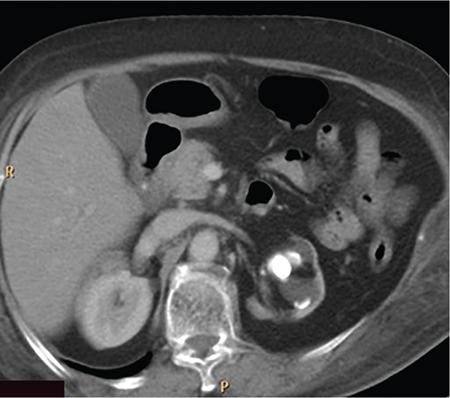

Xanthogranulomatous pyelonephritis (XGP) is a rare, chronic inflammatory condition of the kidneys characterized by renal parenchymal destruction and replacement by lipid laden foamy macrophages. (Xantho means yellow, yellow colour imparted to renal parenchyma and inflammatory masses by abundance of lipid laden macrophages.) It is first described by Schlagenhaufer in 1916. Aetiology is often unclear, however considered multifactorial, mostly as a combination of renal obstruction and recurrent infection/inflammation. Recurrent bacterial infections along with an incomplete immune response to organisms such as Proteus mirabilis, E. coli along with multiple other bacteria are implicated. The disease is most commonly seen in women of middle age group, however elderly and children are also affected. Most commonly, seen to be associated with an obstructive renal calculus, however destruction of the renal parenchyma is due to severe inflammation than obstruction. There is also an increased incidence of diabetes mellitus and other metabolic diseases among the patients. Lymphatic obstruction, malnutrition, arterial insufficiency, venous occlusion and haemorrhage are other factors implicated. In addition, it has been presented as a complication of renal transplant. Various predisposing factors are summarized in the following box. It can occur at any age, but most frequently in the fifth to sixth decades. Female predilection is seen likely due to higher incidence of UTIs and thus struvite (staghorn) calculi. There is also an increased incidence in patients with diabetes mellitus. Most of the cases are associated with a pelvic renal calculus which assumes a staghorn shape (struvite calculi). Along with the subsequent hydronephrosis, chronic inflammation and other precipitating factors mentioned above lead to scarred contracted renal pelvis, dilated calyces and diffuse infiltration of the renal parenchyma by plasma cells and lipid laden macrophages, which may form multiple yellow coloured masses. Microscopic examination shows ulcerated calyceal mucosa which is replaced by necrotic debris and inflammatory cells, mainly polymorphonuclear leukocytes. Granulation tissue with multinucleated macrophages will be seen in the adjacent tissue. The inflammatory zone is associated with plasma cellular infiltrate and bordered by a band of fibrous tissue. Macroscopically and in radiological studies, infiltration of perirenal tissues, psoas muscle, adjacent small bowel, diaphragm and soft tissues are often seen. Involvement of ureter has also been reported. Two main types of XGP are described focal (10%–17%) and diffuse (80%). Focal XGP imitates a renal mass and hence has been described as ‘Great imitator’ main differential being Wilms’ tumour. Focal form of XGP is usually seen in the renal cortex, with no communication with pelvis. An obstructive renal calculus may not be always present. As it often mimic a renal tumour, it is hence considered a pseudotumour. The diffuse type affects the whole kidney and is more common in children. A third, segmental form has also been mentioned. Staging for XGP is proposed by Malek and Elder. There are three stages. Symptoms are highly variable with patients presenting with acute symptoms such as fever, flank pain, UTI similar to pyelonephritis or chronic nonspecific symptoms such as weight loss, malaise and anorexia. On physical examination, a palpable mass in the flank along with tenderness can be elicited. A draining renal cutaneous fistula is seen in 5% of patients. Sometimes the patient can be asymptomatic as well. Lab parameters will show anaemia, raised erythrocyte sedimentation ratio, leukocytosis. Urine analysis may show positive urine culture, microscopic haematuria, proteinuria and pyuria.. Most often urinary tract symptoms are absent, in such cases pyuria and positive urine cultures (95% and 60%, respectively) are present. XGP can also present as a complication of renal transplant and diabetes mellitus. The above-mentioned macroscopic forms (focal and diffuse) are recognized on imaging. Diffuse form accounts for 90% of the cases. Focal form also known as tumefactive form constitutes approximately 10% of cases and sometimes can represent diffuse XGP of one moiety of a duplex system. Cross-sectional imaging is the most important modality for diagnosis as findings in plain radiograph or intravenous urography (IVU) alone is nonspecific. However, ultrasound is the first modality of imaging since it helps in differentiating focal from diffuse form. However, no radiologic features are characteristic of XGP. Diagnosis with plain radiography is not always possible. The main differentials include a cute pyelonephritis, renal cell carcinoma and renal calculus disease and differentiating between them is difficult. Staghorn calculi will be seen most often (75% of cases) in XGP. Renal outline may appear enlarged and fragmented. Perinephric extension of inflammation will produce an ill-defined renal margin. The kidneys will be nonfunctioning on the affected side with no excretion (absent nephrogram seen). Sometimes a partially enhancing and excreting kidneys can be seen. Similar findings are seen in chronic hydronephrosis with associated cortical thinning. Focal lesions show no function or a patchy nephrogram. Associated splaying and stretching of the calyces can be seen. It is commonly the first imaging modality. Ultrasonography findings usually demonstrate an enlarged kidney with loss of corticomedullary differentiation and maintained reniform shape. The renal pelvis is small due to fibrosis. Calyces will appear dilated with an echogenic rim. Cortical thinning occurs with replacement of renal parenchyma by hypoechoic masses which represent hydrocalyces, small abscesses or granulomas. As these hypoechoic areas are not simple fluid-filled spaces, they may not show posterior acoustic enhancement and thus differentiating from simple hydronephrosis, latter will show dilated calyces which are sharply defined and demonstrate post acoustic enhancement. A staghorn calculus will be usually demonstrated, may or may not show posterior acoustic shadowing. Ultrasonography can easily differentiate diffuse form from focal form. There is generalized enlargement of kidneys with focal hypoechoic areas described above, in case if diffuse XGP. Whereas the focal form may appear as a focal heterogeneous mass, which can be often misdiagnosed as a tumour. The main disadvantage of ultrasonography is that it is less sensitive than other modalities in demonstrating extrarenal spread. Also, similar appearances are also seen in simple hydronephrosis associated with renal calculus, pyonephrosis, renal TB, cystic neoplasm and lymphoma. CT is the main modality for assessing perirenal extension and is essential for preoperative evaluation. The findings are most helpful in reaching the diagnosis. In diffuse disease, generalized enlarged nonfunctioning kidney with a staghorn calculus will be seen. Calculus is usually located centrally within the pelvis causing obstruction (Fig. 10.12.2.3.1). Although the reniform shape is usually maintained, the parenchyma is usually destroyed and replaced by hypodense masses of low attenuation (–10 to 30 Hounsfield units [HU]). These dilated cavities and abscesses filled with pus and debris give a multilocular appearance that has been described similar to the paw print of a bear. This sign is characteristic of XGP and has been described as ‘bear paw sign’. Perinephric fat stranding and thickening of Gerota’s fascia is often seen. Calcifications in the xanthomatous masses are easily identified in CT scan. Intrarenal cortical abscesses may show small gas collections within. Renal atrophy has also been described rarely.